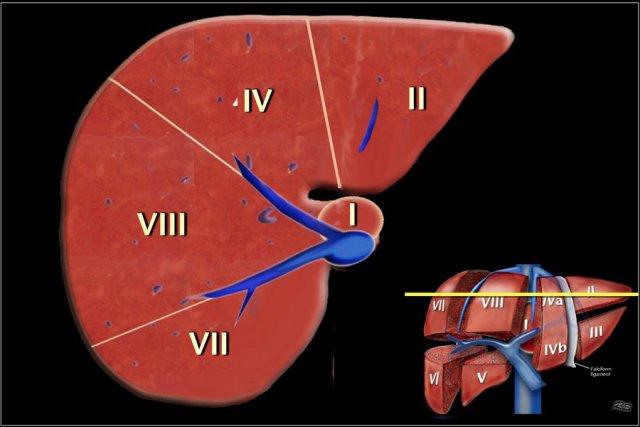

Nhà phẫu thuật và giải phẫu học người Pháp Claude Couinaud là người đầu tiên chia gan thành tám phân thùy độc lập về mặt chức năng, cho phép cắt bỏ từng phân thùy mà không gây tổn thương cho các phân thùy khác.

Giải phẫu phân thùy

Phân loại Couinaud

- Mặt phẳng của tĩnh mạch gan phải chia thùy gan phải thành phân thùy trước và phân thùy sau.

- Mặt phẳng của tĩnh mạch gan giữa chia gan thành thùy phải và thùy trái, hay còn gọi là nửa gan phải và nửa gan trái. Mặt phẳng này chạy từ tĩnh mạch chủ dưới đến hố túi mật.

- Mặt phẳng rốn chạy từ dây chằng liềm đến tĩnh mạch chủ dưới, chia thùy trái thành phần trong (phân thùy IV) và phần ngoài (gồm phân thùy II và III). Đây là mặt phẳng định hướng đứng dọc duy nhất không được xác định bởi một tĩnh mạch gan.

Đánh số phân thùy

Gan có tám phân thùy.

Phân thùy IV đôi khi được chia thành phân thùy IVa và IVb theo Bismuth.

Các phân thùy được đánh số theo chiều kim đồng hồ.

Phân thùy I (thùy đuôi) nằm ở phía sau.

Phân thùy này không thể quan sát được trên mặt phẳng nhìn thẳng.